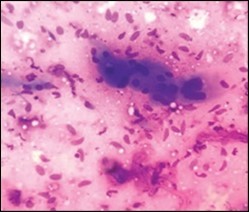

On gross examination, a tan coloured, gritty nodule, confined to the sternocleidomastoid muscle is delineated. Characteristically, smears obtained by fine needle aspiration cytology are composed of bland appearing, plump or normal fibroblasts and proliferating fibroblasts with an admixture of degenerative, atrophic skeletal muscle cells, giant myocytes with several nuclei, scattered, bare, bland nuclei or cells with fragmented, wispy cytoplasm and parallel aggregates of fibroblasts. The background is clear and devoid of cellular or nuclear debris. Sheets of spindle-shaped fibroblasts, atrophic muscle fibres and regenerating, multinucleated muscle giant cells are intermingled with the fibroblastic component 5, 6.

Figure 4.Fine needle aspiration cytology of fibromatosis colli delineating aggregates of plump, spindle-shaped cells admixed with fibroblasts, fibro-connective tissue fragments and intermingled red cell extravasation 11